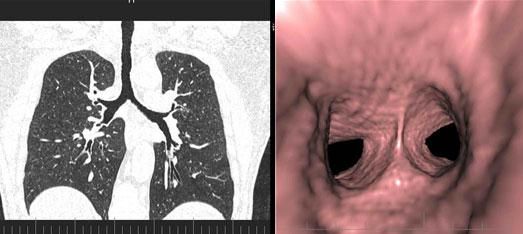

3、肺動脈血管成像:

三、先進的仿真内鏡技術:

從多角度,多平面分析空腔髒器病變,可應用于胃、結腸、血管、氣管支氣管、膽道等仿真内鏡檢查,大大提高了病變的檢出率和診斷的準确性。